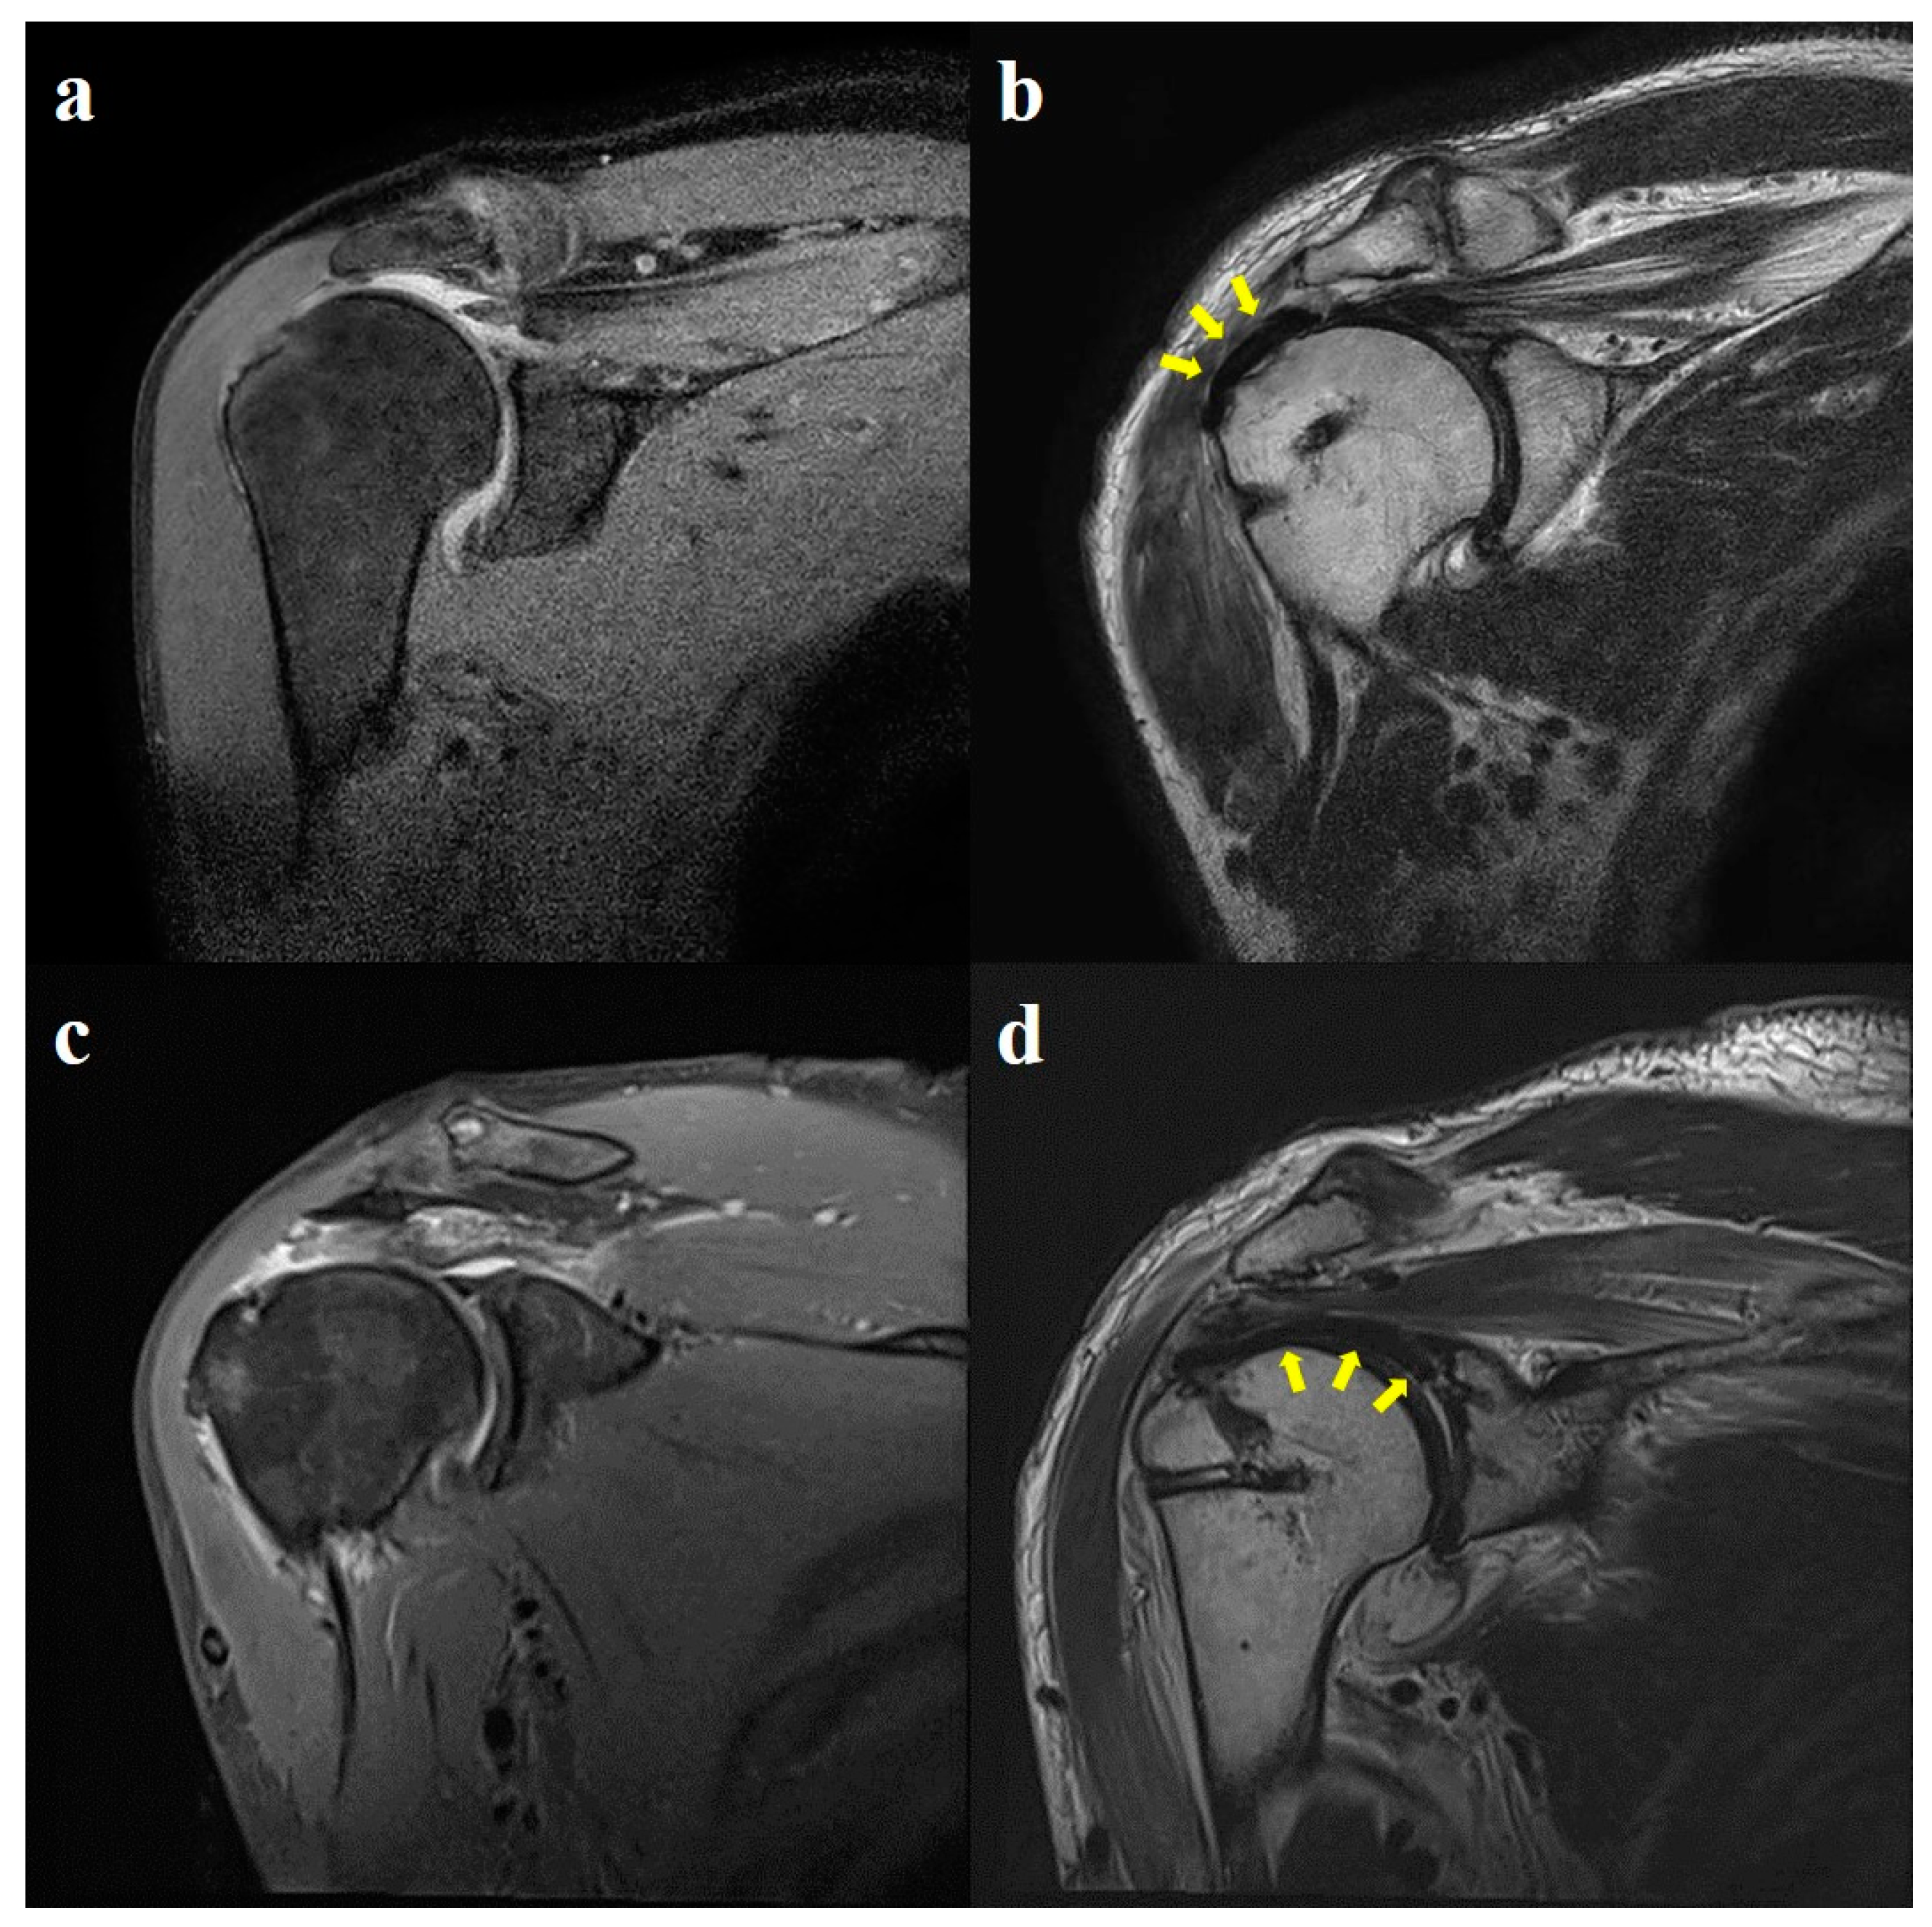

2.4. Radiological Evaluation

3.4. Radiological Outcomes